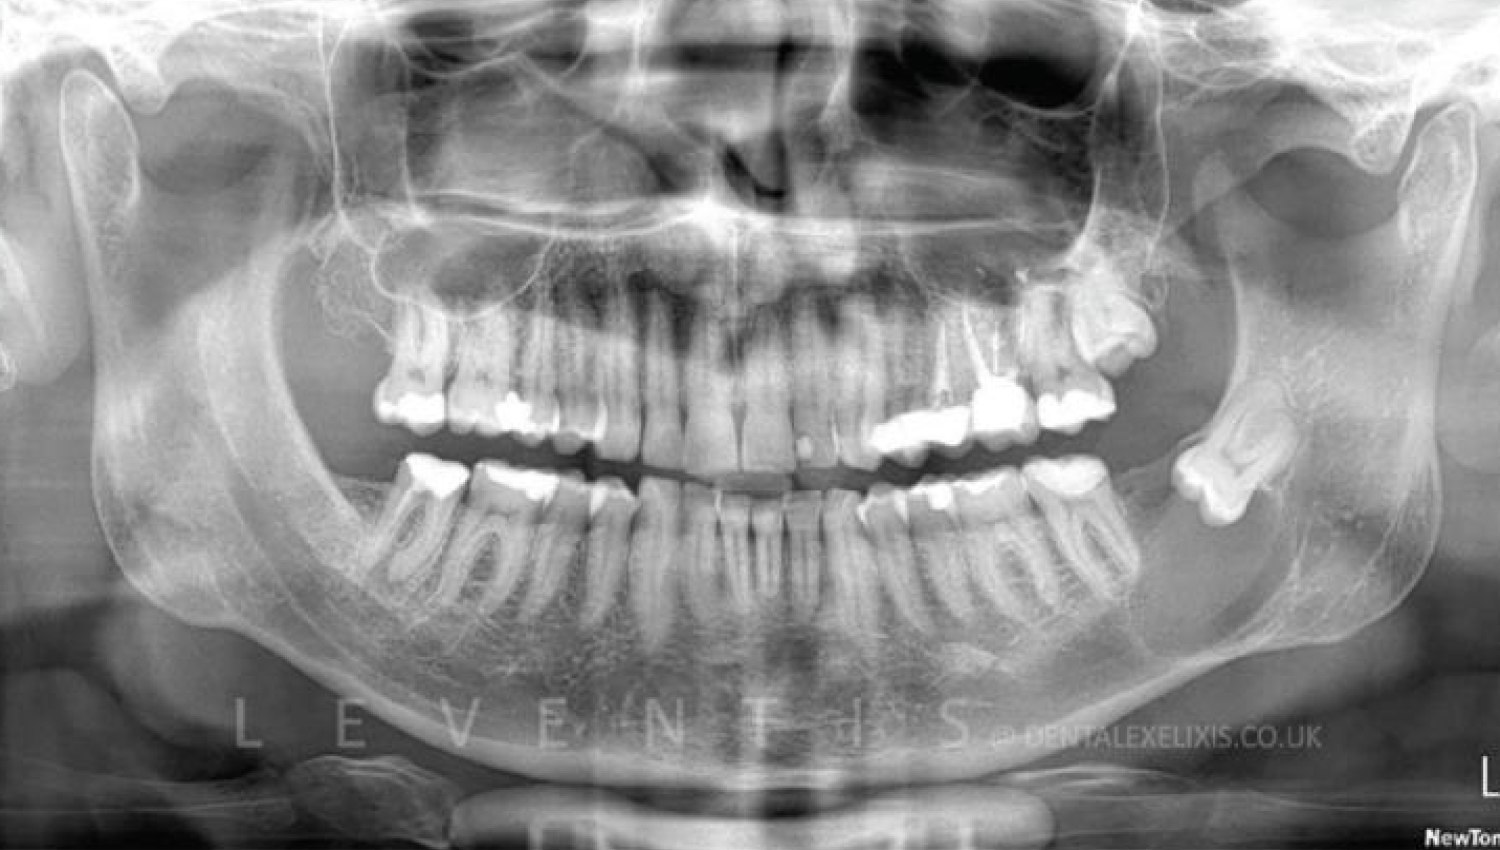

- Male, 26 years old.

- An impacted third molar and the

- associated dentigerous cyst..

2. Initial periapical x-ray.

6.Clinical and radiological views 6 months post-operaticely. Healthy periodontal tissues wiht no bleeding on probing and < 3mm probing depth on the distal aspect of the second molar. The area is covered with keratinized soft tissues, and the architecture of the ridge is adequately restored.The main concern and objective was to fully regenerate the bone defect distally to the second molar, to prevent furhet bone loss and periodontal defects distally to the second molar.